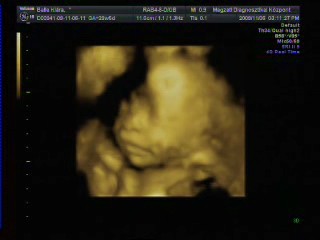

Kép Zsomborka 28+4

Kép Zsimbi talpacska